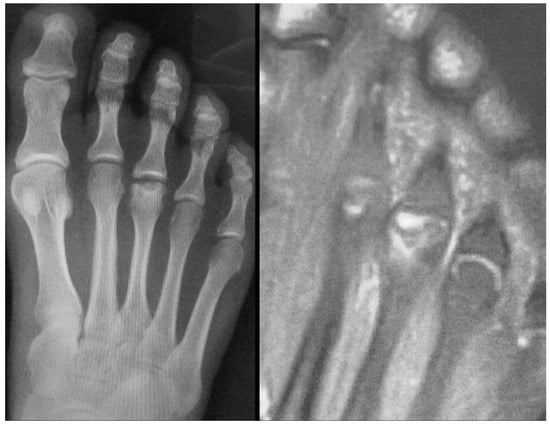

Plain radiographs are the cornerstone of imaging in the diagnosis of lesser metatarsal osteochondrosis. In the early stages of the disease, when supported by a suggestive clinical presentation, obtaining a comparative radiograph of the contralateral foot can be a useful diagnostic tool (Figure 9).

Figure 9.

Radiograph of a symptomatic 10-year-old female patient showing early sclerosis and flattening of the second metatarsal head on the left foot, compared to the contralateral side.

In the later stages, radiographs may reveal characteristic changes including subchondral sclerosis, fragmentation, and flattening of the affected metatarsal head (Figure 10 and Figure 11). In some cases, the presence of joint space narrowing or bony irregularities may also be observed. However, early changes, such as bone marrow edema or subtle cartilage damage, may not be visible on standard radiographs. MRI is particularly useful in the early stages of the disease, as it can detect bone marrow edema, which is a sign of active bone inflammation and necrosis, even before structural changes become apparent on radiographs (Figure 10, Figure 11 and Figure 12).